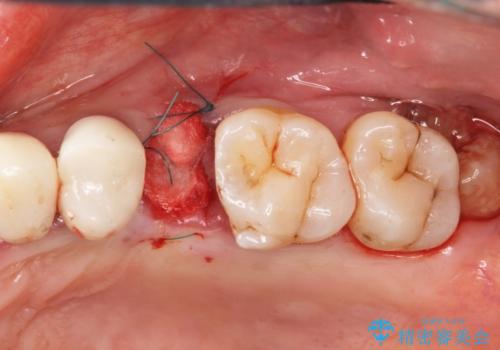

最終的なブリッジの清掃性を高めるため、歯ぐきのボリュームがこれ以上減少しないよう抜歯時に歯槽堤保存術を行うような工夫をしています。

治療前よりも高い位置で歯ぐきが保たれ、清掃性の高いブリッジ治療を行うことができました。